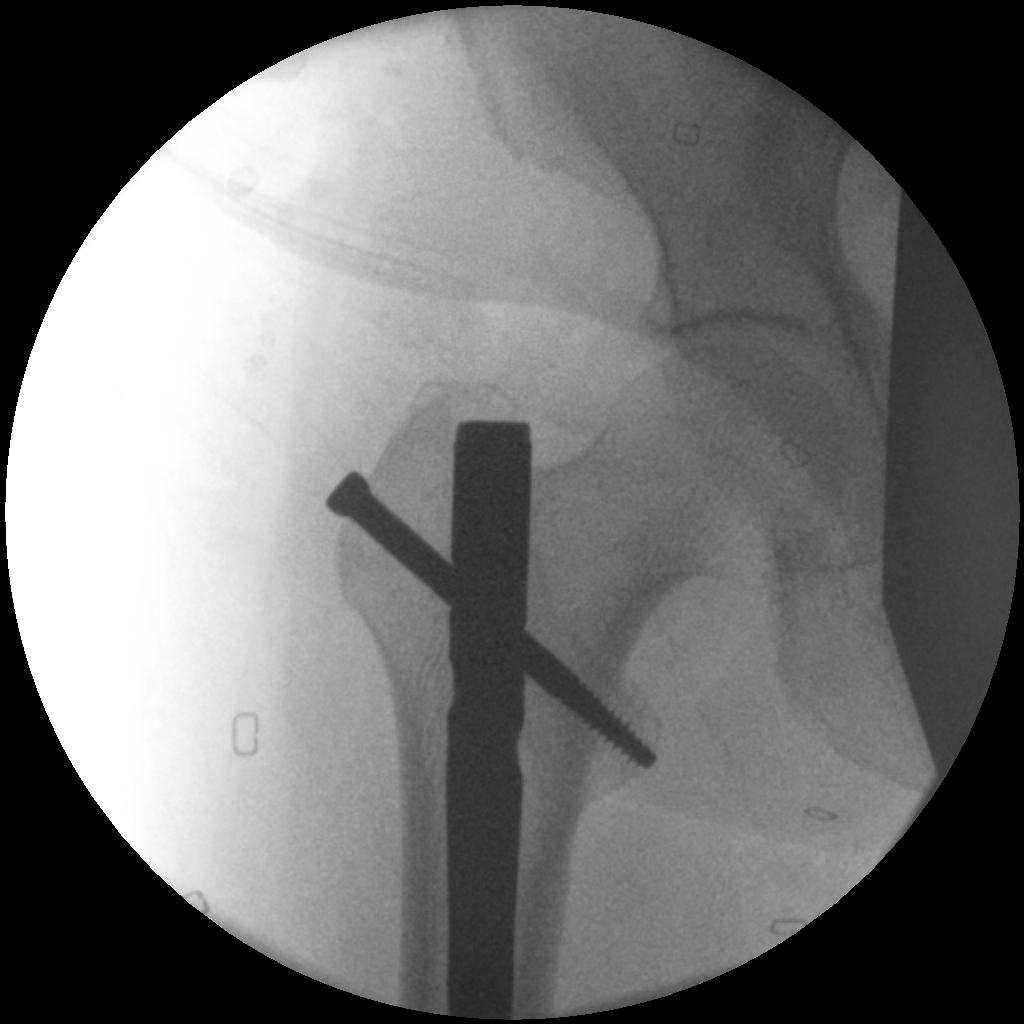

2. NOF (Neck of Femur) + Femoral shaft fracture

Must pay attention first to meticulous NOF ORIF

Options

1. Pin and Plate NOF / Retrograde Nail

2. Pin and Plate NOF / Plate femur

3. Reconstruction Nail

- difficult to anatomically reduce NOF

- increased incidence NOF non union

Difficult scenario

- antegrade IMN in place before diagnosis of NOF fracture

- if undisplaced, can place screws anterior to nail

- if displaced must remove nail

Results

Ostrum et al. CORR 2014

- 95 cases treated with proximal screws / sliding hip screws inserted first

- retrograde IMN second

- 98% union rate femoral neck

- 91% union rate femoral shaft